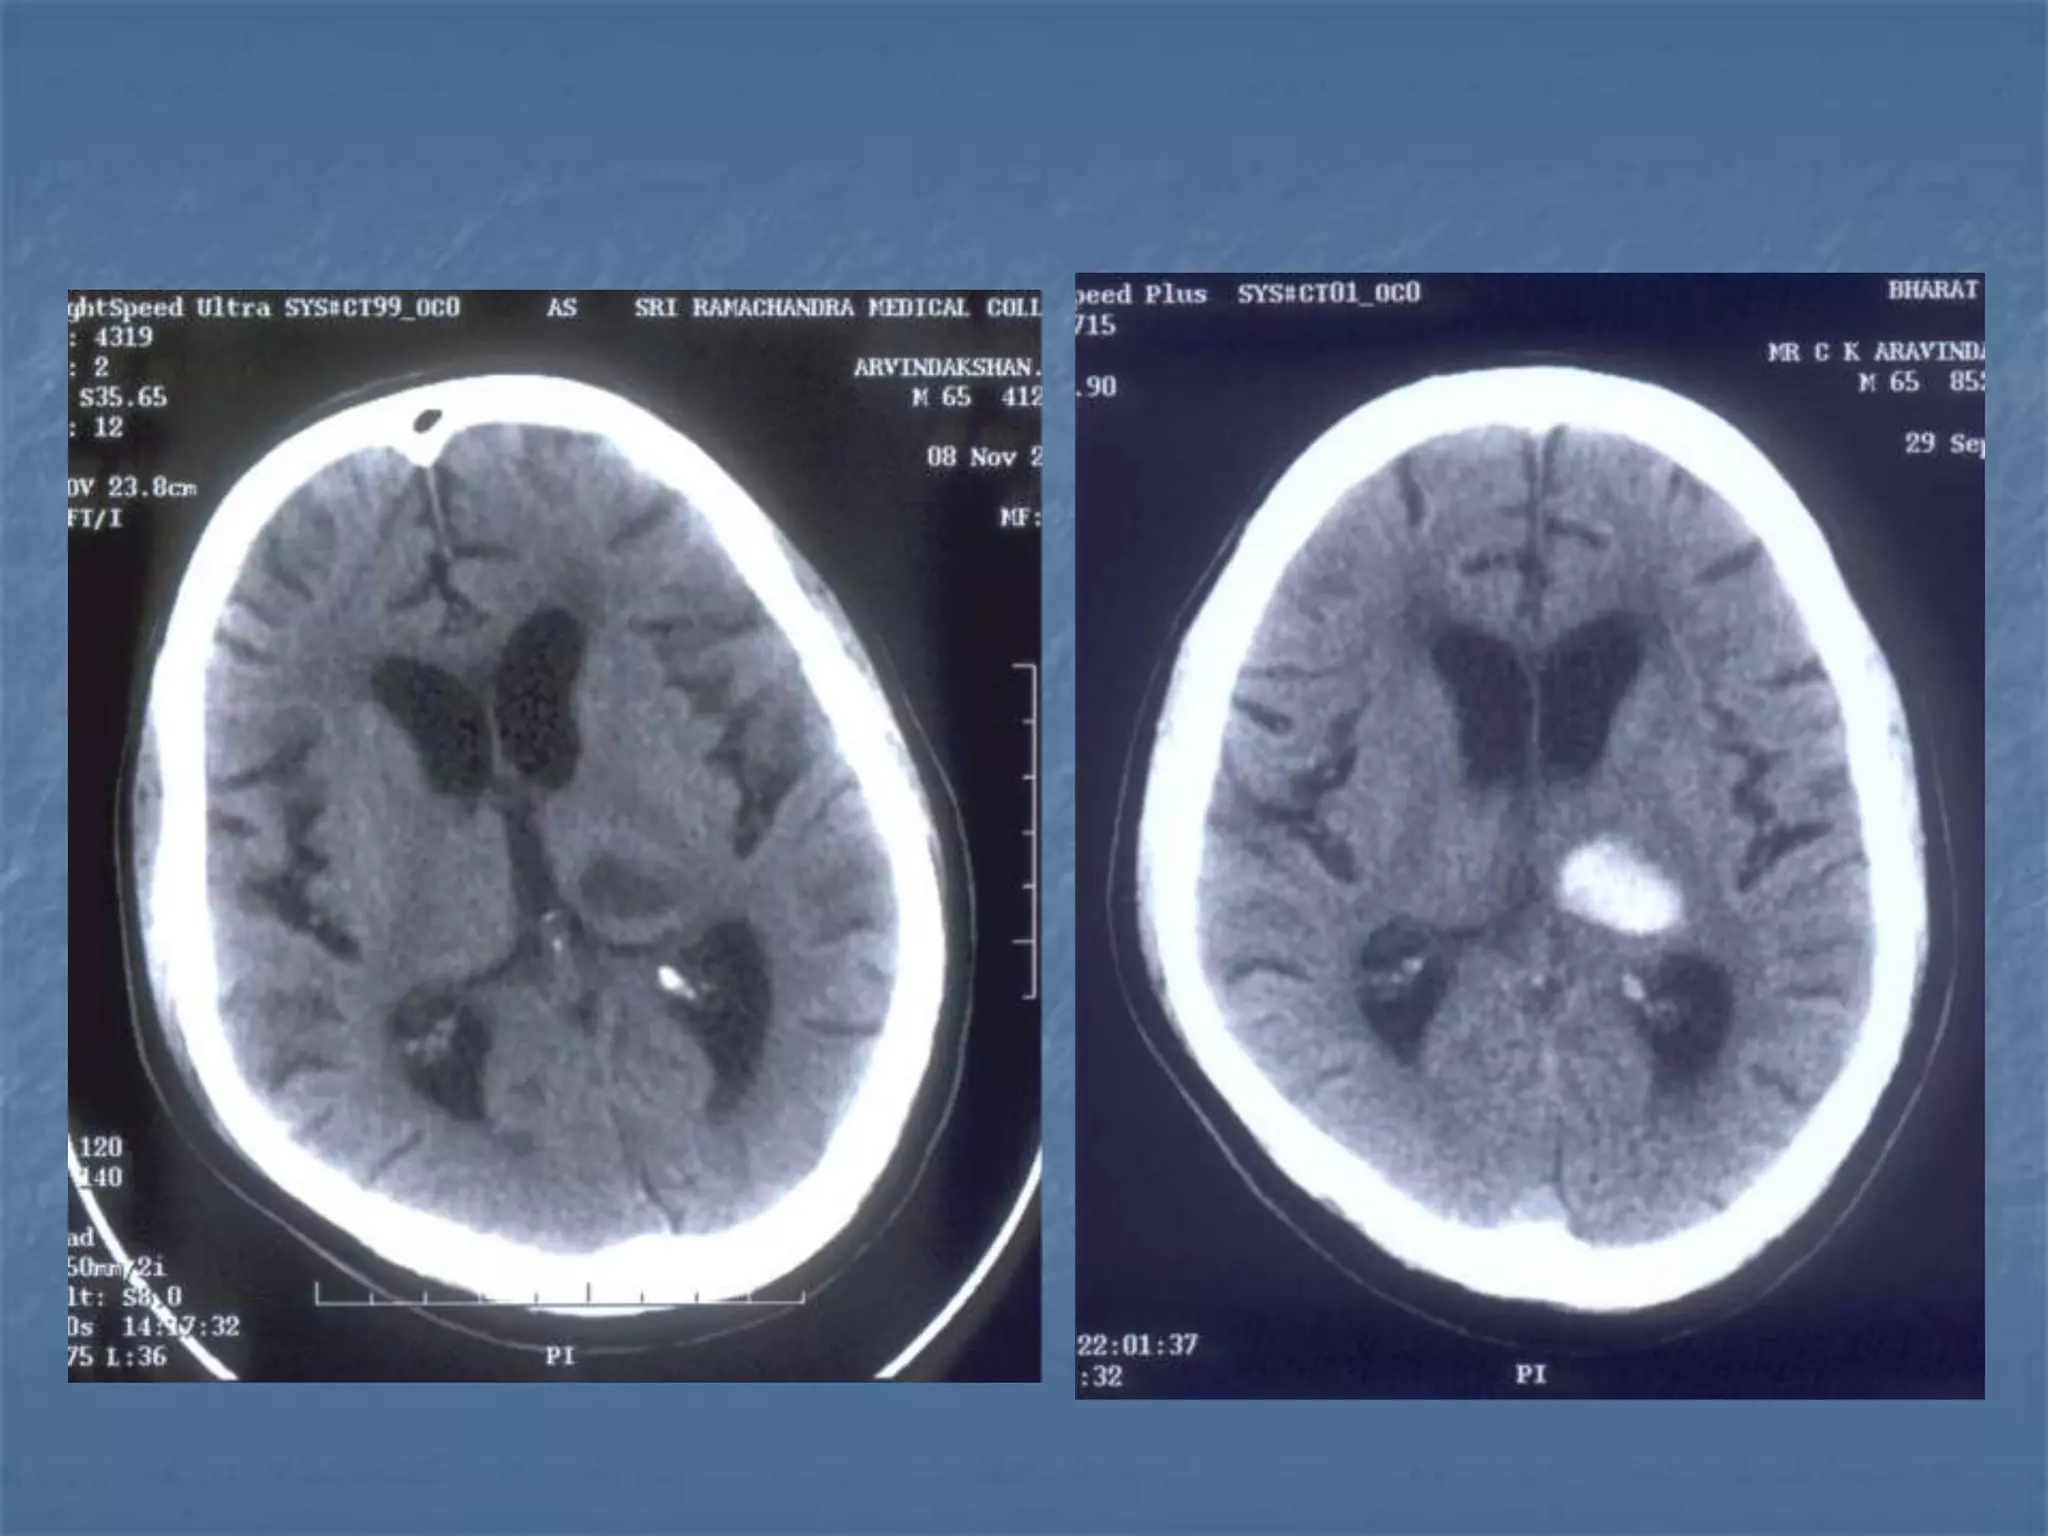

Hypertensive Hemorrhage

 Hypertensive hemorrhage accounts for

approximately 70-90% of non-traumatic primary

intracerebral hemorrhages. It is commonly due to

vasculopathy involving deep penetrating arteries

of the brain. Hypertensive hemorrhage has a

predilection for deep structures including the

thalamus, pons, cerebellum, and basal ganglia,

particularly the putamen and external capsule.

Thus, it often appears as a high-density

hemorrhage in the region of the basal ganglia.

Blood may extend into the ventricular system.

Intraventricular extension of the hematoma is

associated with a poor prognosis.

Haemorrhagic StrokeEtiology

 Hypertension

 Vascular malformation

 Aneurysm

 Trauma

 Amyloid angiopathy

 Tumor

 Coagulopathy

 Hemorrhages can occur in the intraparenchymal,

subarachnoid, intraventricular, subdural and

extradural spaces.

 Location of hypertensive hemorrhage:

Putamen, external capsule, thalamus, pons,

cerebellum, subcortical white matter